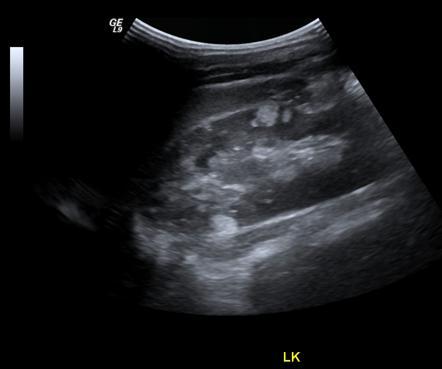

Hypoechoic renal cortex